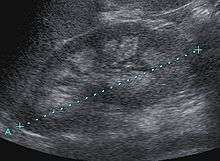

Nephrocalcinosis, once known as Albright's calcinosis after Fuller Albright, or Anderson-Carr kidneys, is a term originally used to describe deposition of calcium salts in the renal parenchyma due to hyperparathyroidism. It is now more commonly used to describe diffuse, fine, renal parenchymal calcification on radiology.[1] During its early stages, nephrocalcinosis is visible on x-ray, and appears as a fine granular mottling over the renal outlines. These outlines eventually come together to form a dense mass.[2] It is most commonly seen as an incidental finding with medullary sponge kidney on an abdominal x-ray. However, it may be severe enough to cause (as well as be caused by) renal tubular acidosis or even end stage renal failure, due to disruption of the renal tissue by the deposited calcium.